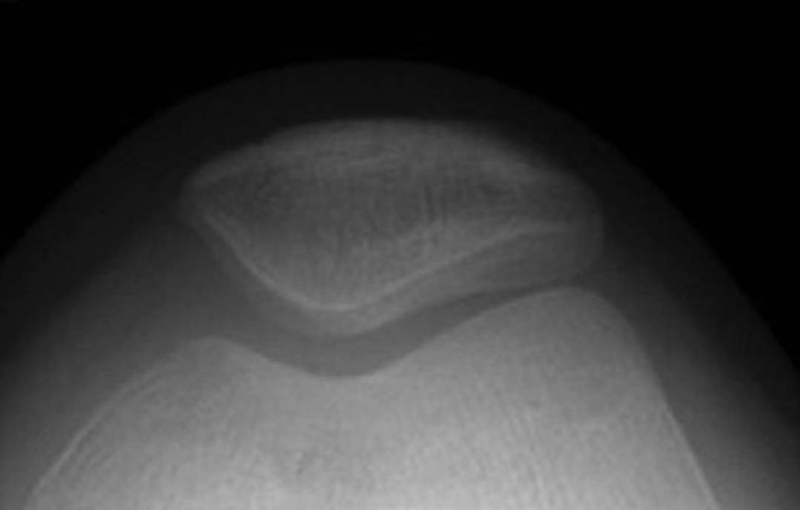

WibergⅡ型(图11):髌骨内侧关节面较小,为平坦或轻度凹陷的形状,而外侧关节面宽大,轮廓为凹面,髌骨嵴稍偏于内侧,约占65%。

图11 WibergⅡ型髌骨轴位X线片